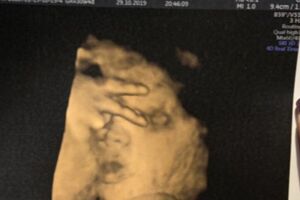

你在拍我嗎?最狂胎兒手比YA 準媽媽哭笑不得